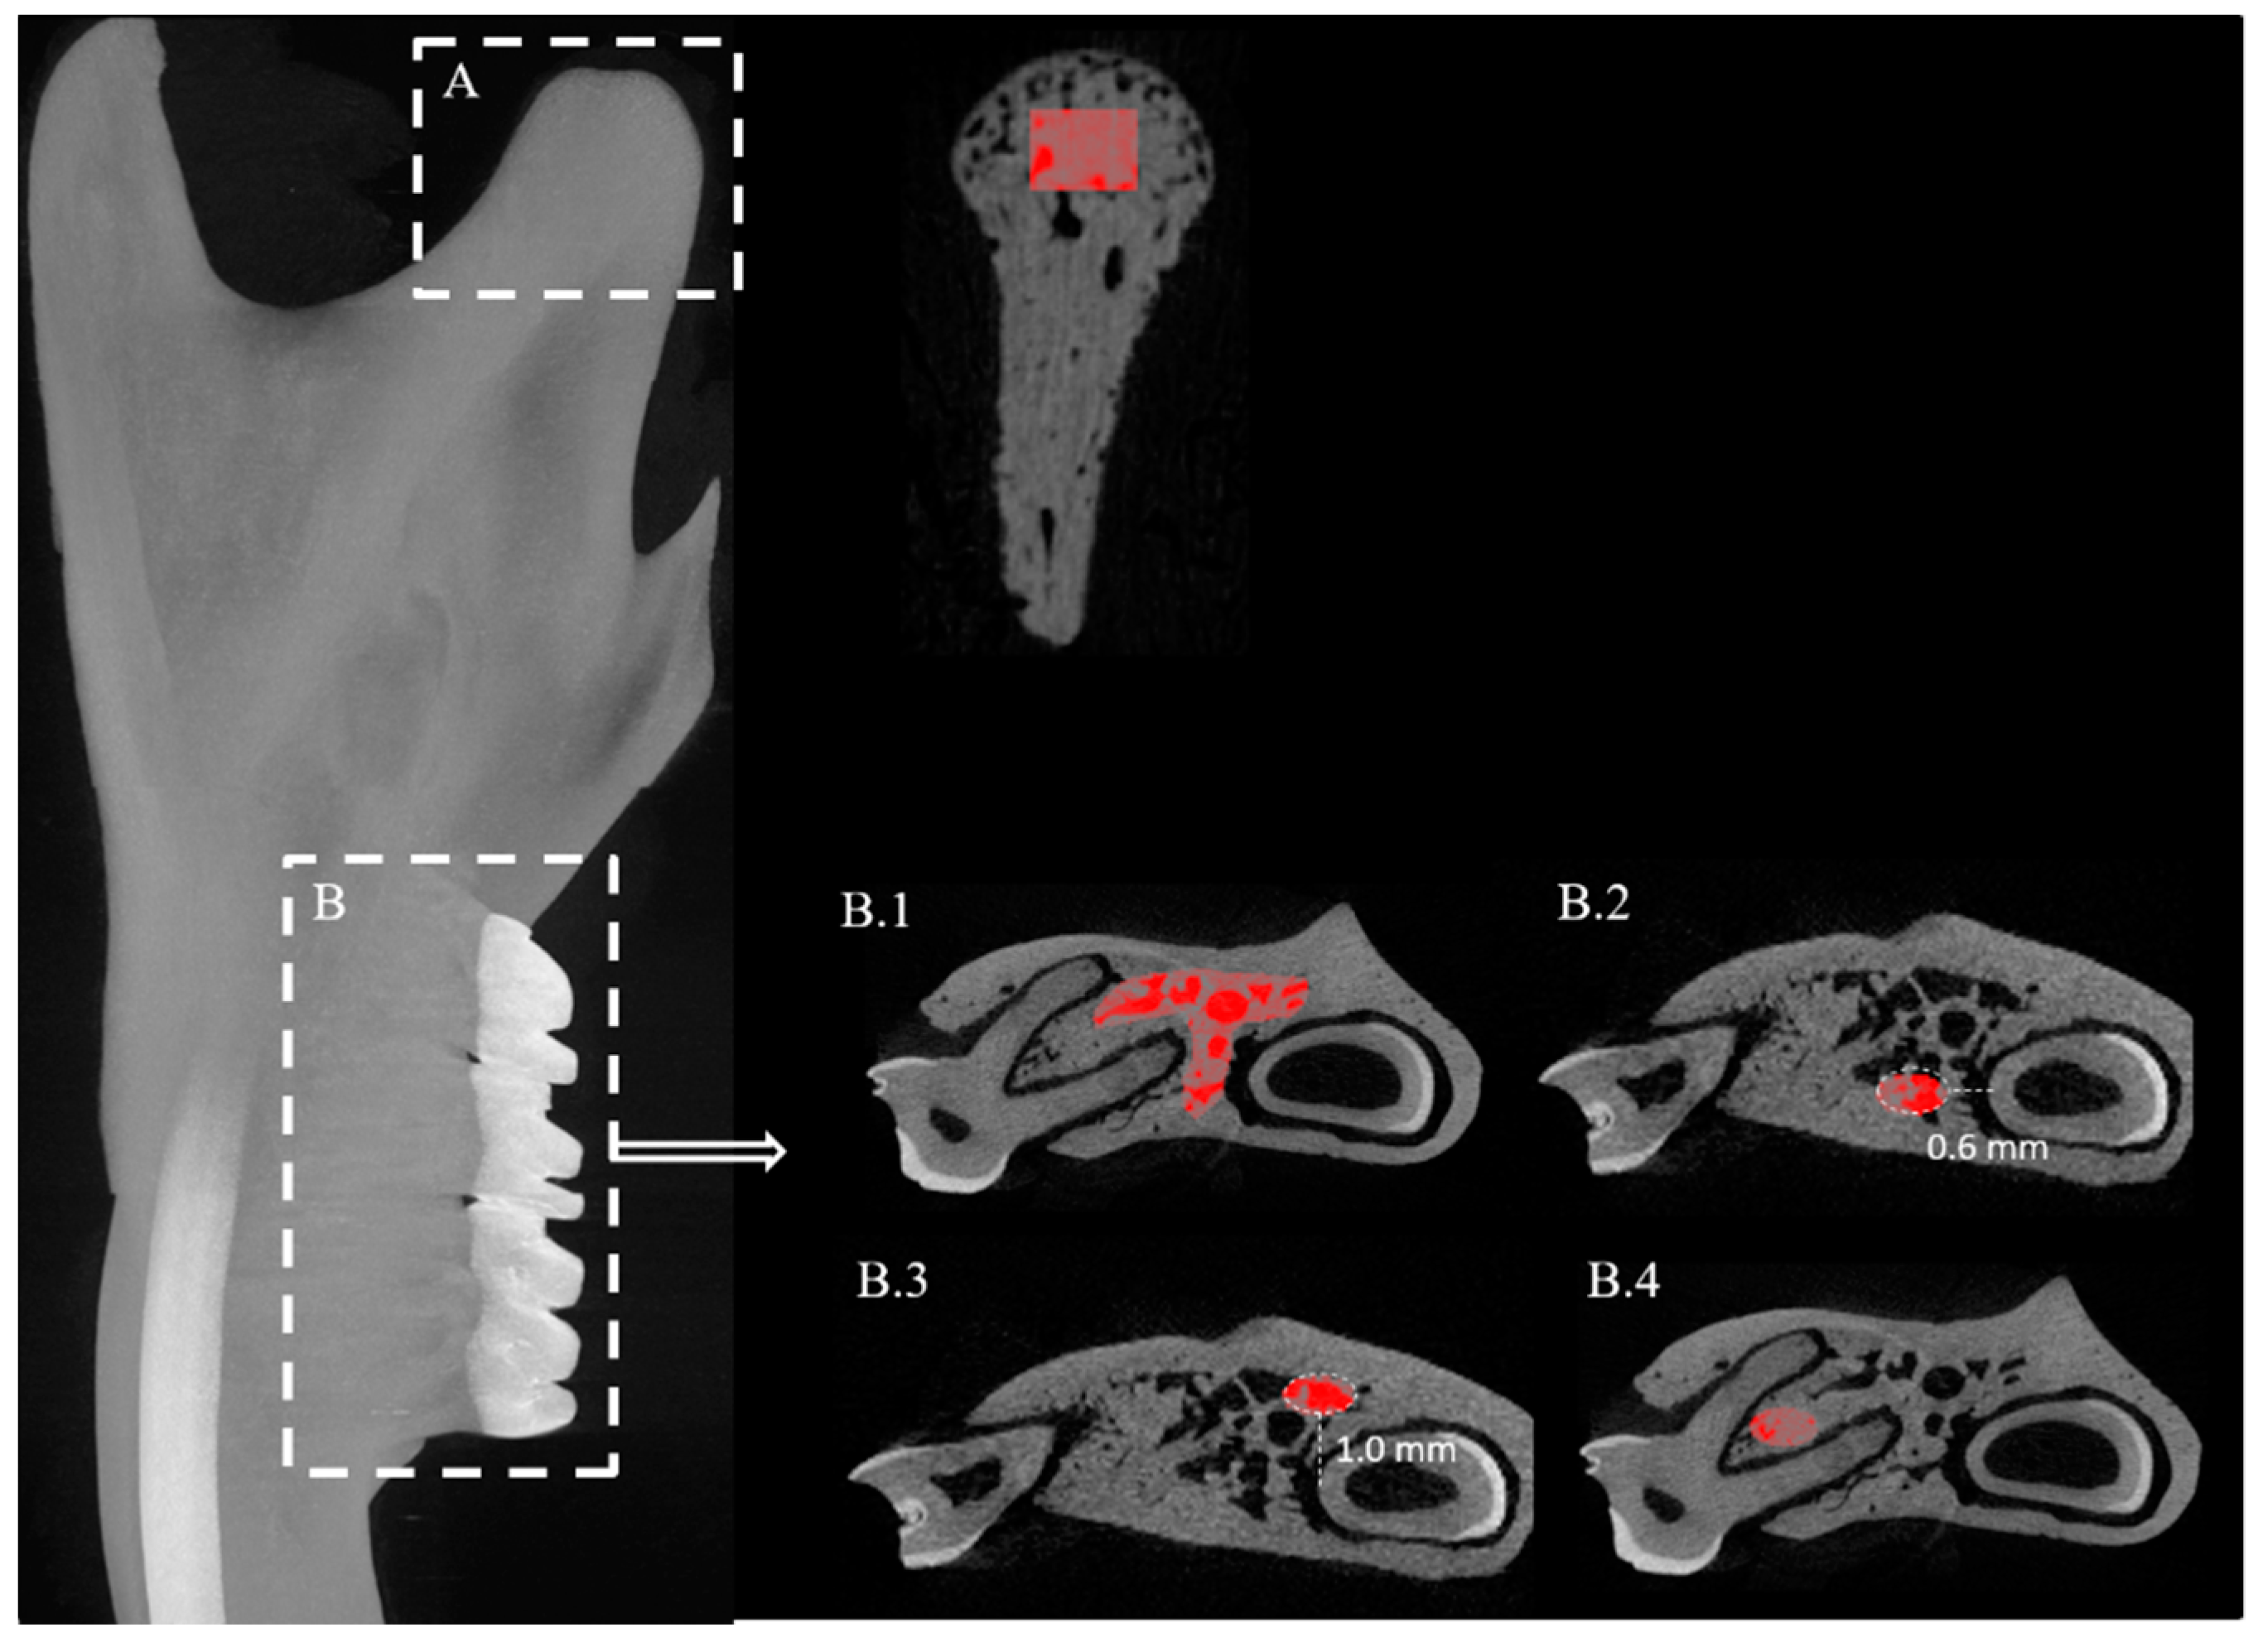

2.2. Mandible

4.5. Analysis of the Mandible